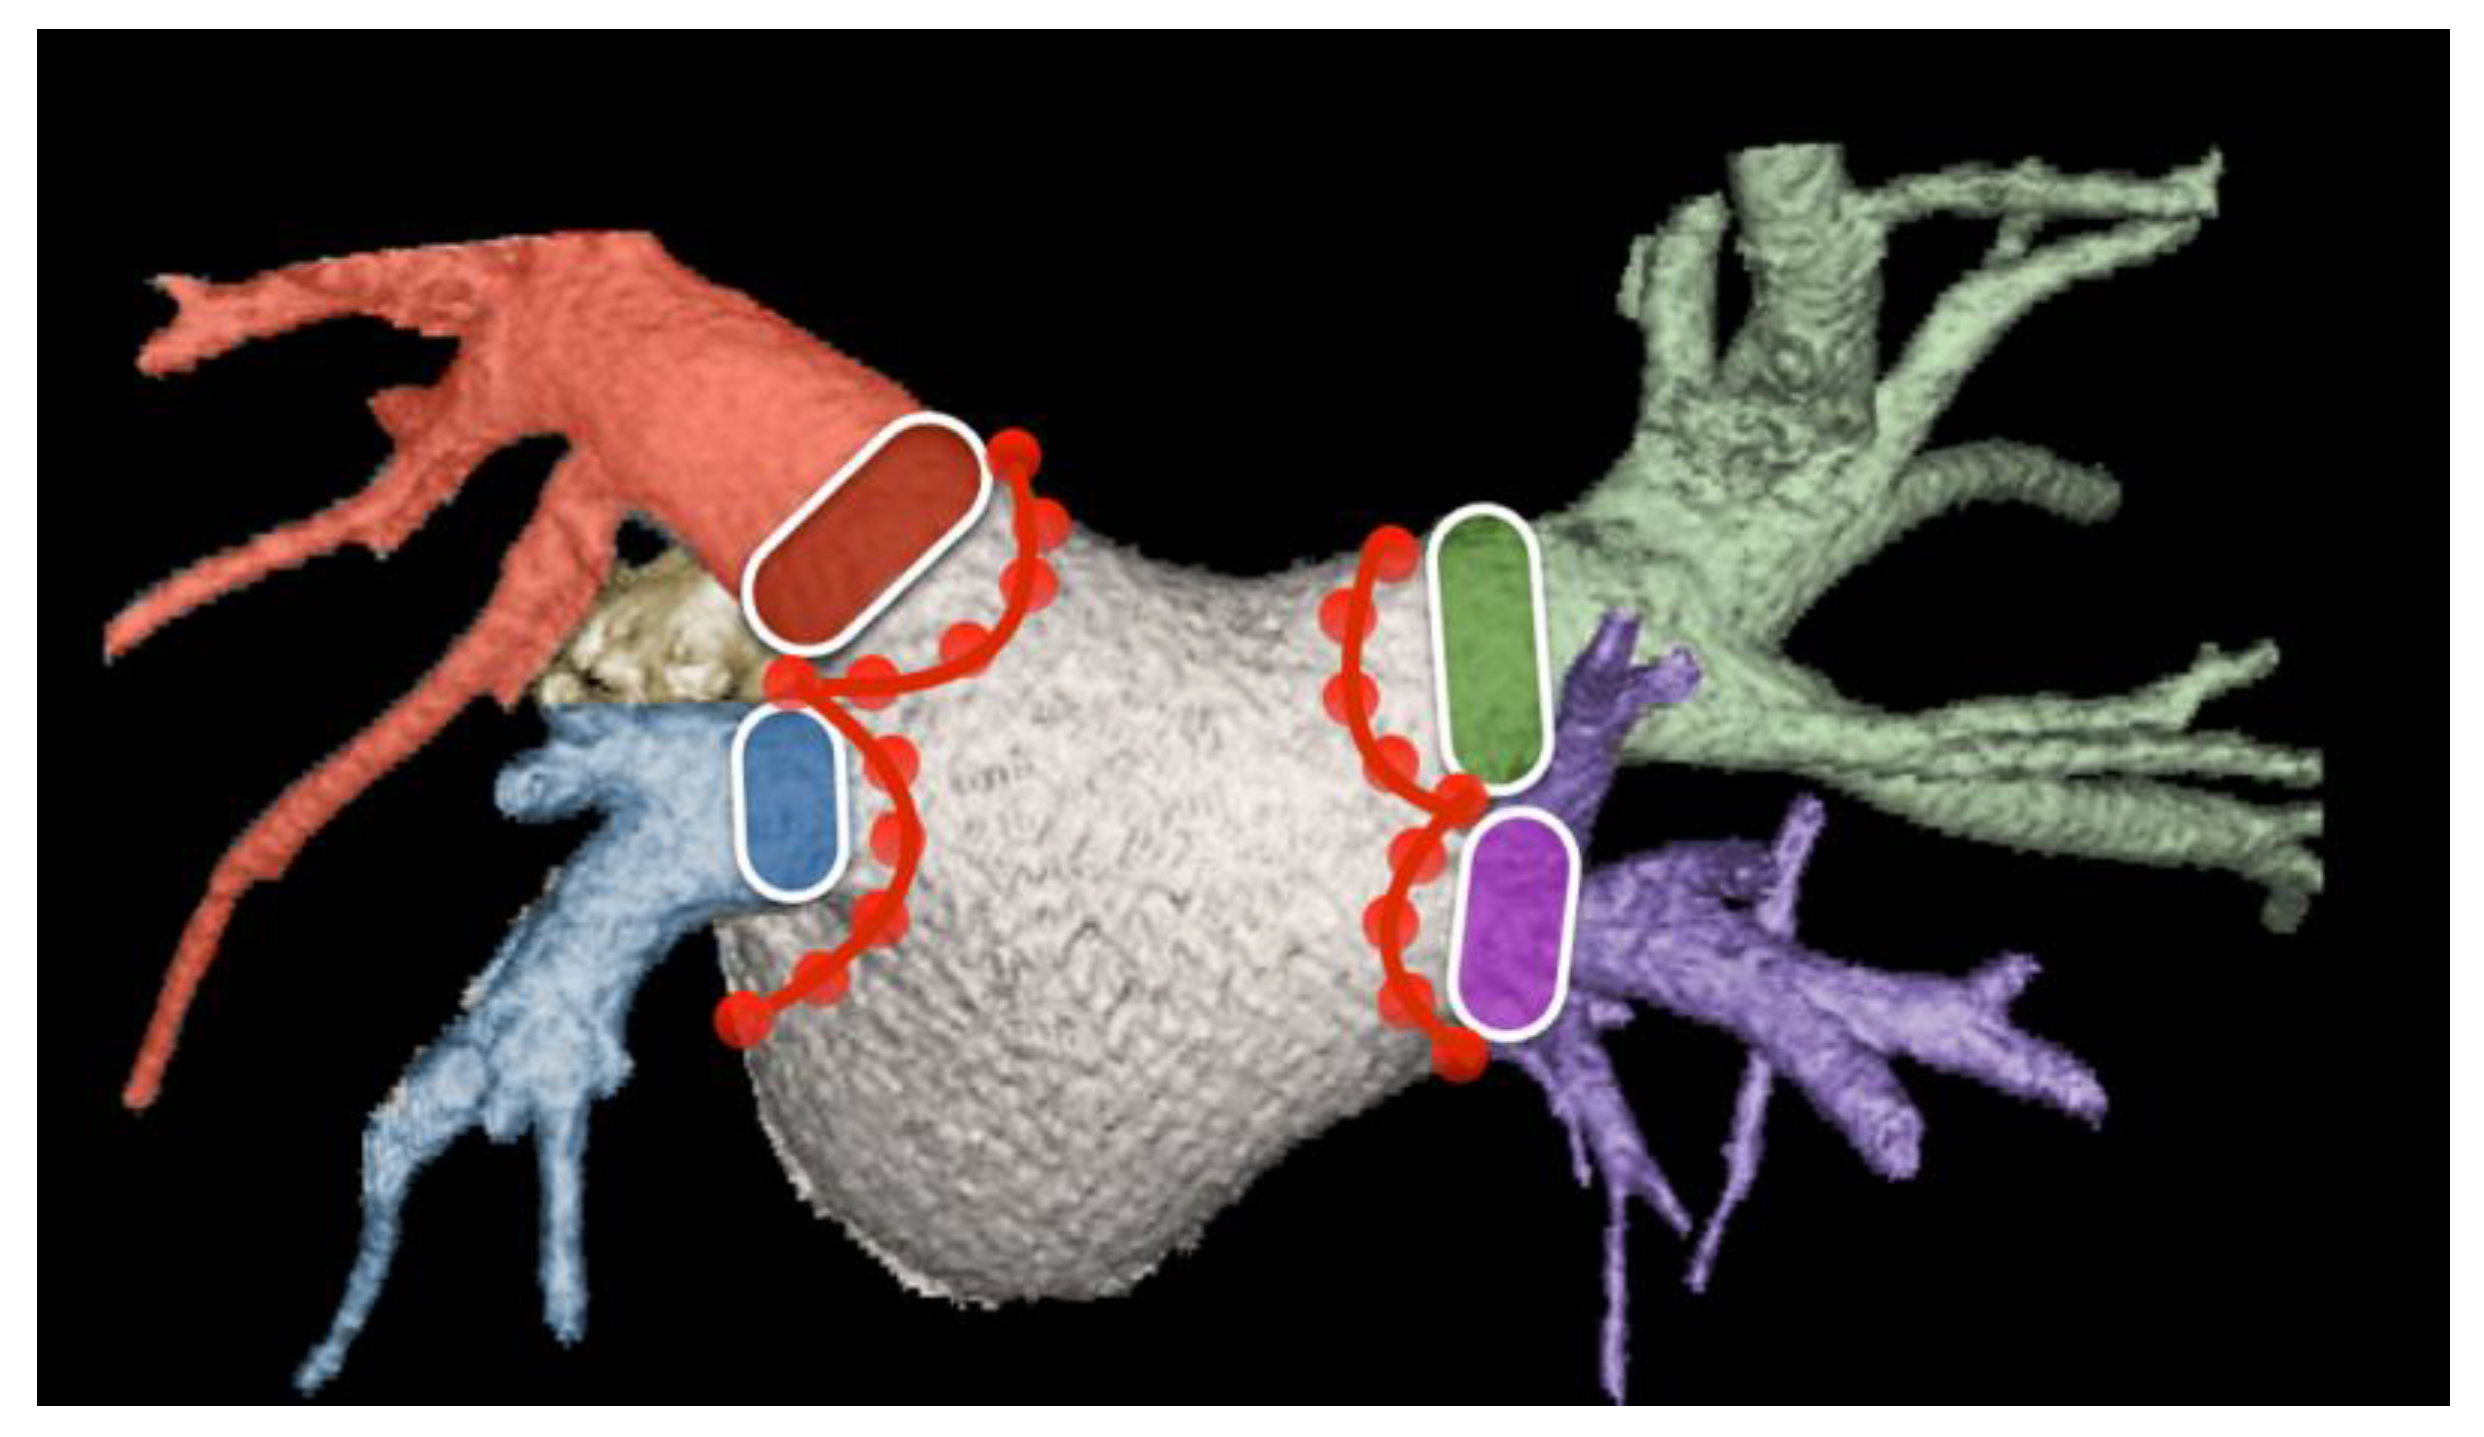

- Hell, M.M.; Emrich, T.; Kreidel, F.; Kreitner, K.-F.; Schoepf, U.J.; Münzel, T.; von Bardeleben, R.S. Computed tomography imaging needs for novel transcatheter tricuspid valve repair and replacement therapies. Eur. Heart J. Cardiovasc. Imaging 2020, 22, 601–610. [Google Scholar] [CrossRef] [PubMed]

- van Rosendael, P.J.; Kamperidis, V.; Kong, W.K.; van Rosendael, A.R.; van der Kley, F.; Ajmone Marsan, N.; Delgado, V.; Bax, J.J. Computed tomography for planning transcatheter tricuspid valve therapy. Eur. Heart J. 2017, 38, 665–674. [Google Scholar] [CrossRef] [PubMed]

- Faletra, F.F.; A Leo, L.; Paiocchi, V.L.; A Schlossbauer, S.; Borruso, M.G.; Pedrazzini, G.; Moccetti, T.; Ho, S.Y. Imaging-based tricuspid valve anatomy by computed tomography, magnetic resonance imaging, two and three-dimensional echocardiography: Correlation with anatomic specimen. Eur. Heart J. Cardiovasc. Imaging 2019, 20, 1–13. [Google Scholar] [CrossRef]